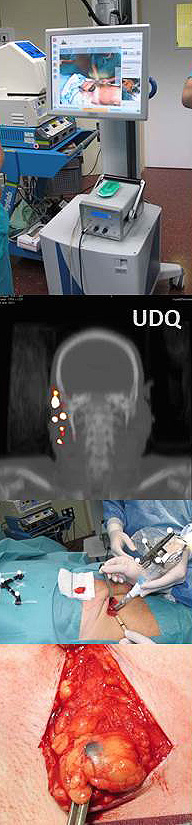

CIRUGÍA DE MOHS

Este técnica está considerada como una de las más efectivas para el tratamiento del cáncer cutáneo localizado. Está especialmente indicada en carcinomas (infiltrantes o clínicamente mal delimitados) o que estén situados en zonas críticas anatómicas (periorbitaria, periauricular, perinasal).

Dicha técnica lleva el nombre de su autor Dr. Frederic Mohs, que posteriormente modificó su alumno Tromovitch con la técnica actual "Cirugía microcontrolada en fresco de Mohs-Tromovitch" aunque en el entorno especializado se donomina por consenso "CMM" (Cirugía Micrográfica de Mohs)

Aunque existen diferentes variedades, dicha técnica consiste esencialmente en extirpar el tumor en su totalidad mediante la ayuda de un complejo estudio microscópico de las piezas operatorias, asegurando que se ha llegado a tejido sano sin excesivo detrimento de éste. Existe controversia en cuanto a su indicación y efectividad en otros tumores (melanoma, sarcoma).

Para su realización se requiere una gran experiencia, tanto quirúrgica como histopatológica.

GANGLIO CENTINELA

Un tumor maligno puede tener la capacidad de invadir y afectar otras estructuras del organismo (capacidad de metástasis). Una de las vías principales de la metástasis es la vía linfática, con la posibilidad de que, en una primera fase, las células tumorales queden estacionadas en los ganglios linfáticos. Por ello, el poder conocer esta circunstancia será de gran utilidad para establecer una valoración más precisa en cuanto al diagnóstico, tratamiento y pronóstico del paciente.

La biopsia selectiva del ganglio centinela (BSGC), consiste en localizar el primer ganglio, de la región ganglionar correspondiente, que pudiera estar afectado.

Técnicamente la BSGC, se efectúa con la colaboración de un equipo de Medicina nuclear. El procedimiento consiste en realizar una infiltración peritumoral de una sustancia hidrocoloide que sirve como transporte por la vía linfática de un isótopo radioactivo o radiotrazador (Tecnecio 99) que se depositará secuencialmente en la región ganglionar pertinente, donde el primer ganglio que quede marcado por el isótopo se identificará como ganglio centinela. La detección del ganglio, por imágen, se realiza mediante una linfogammagrafía o un SPECT-CT, indicando en que lugar anatómico está situado el ganglio centinela. Posteriormente en el quirófano, mediante una gammasonda nuclear, se detectará su situación exacta en la región ganglionar marcada por el isótopo y así poder proceder a su extirpación y estudio anatomopatológico.

Esta técnica está especialmente indicada en los melanomas con un Breslow superior a 1 milímetro, o en melanomas con un Breslow inferior a 1 milímetro pero con factores de riesgo tipo ulceración o índice mitótico mayor de 1x campo, aunque también está indicada en otros tumores metastizantes (carcinoma espinocelular).

En el caso que el ganglio centinela este afectado, se procederá a determinar si el paciente es susceptible a otros tratamientos complementarios (vaciado ganglionar, terapia adyuvante).